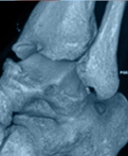

Déviation du premier orteil ou HALLUX VALGUS

L’hallux valgus est une déviation de la base du premier orteil ou gros orteil (hallux en latin